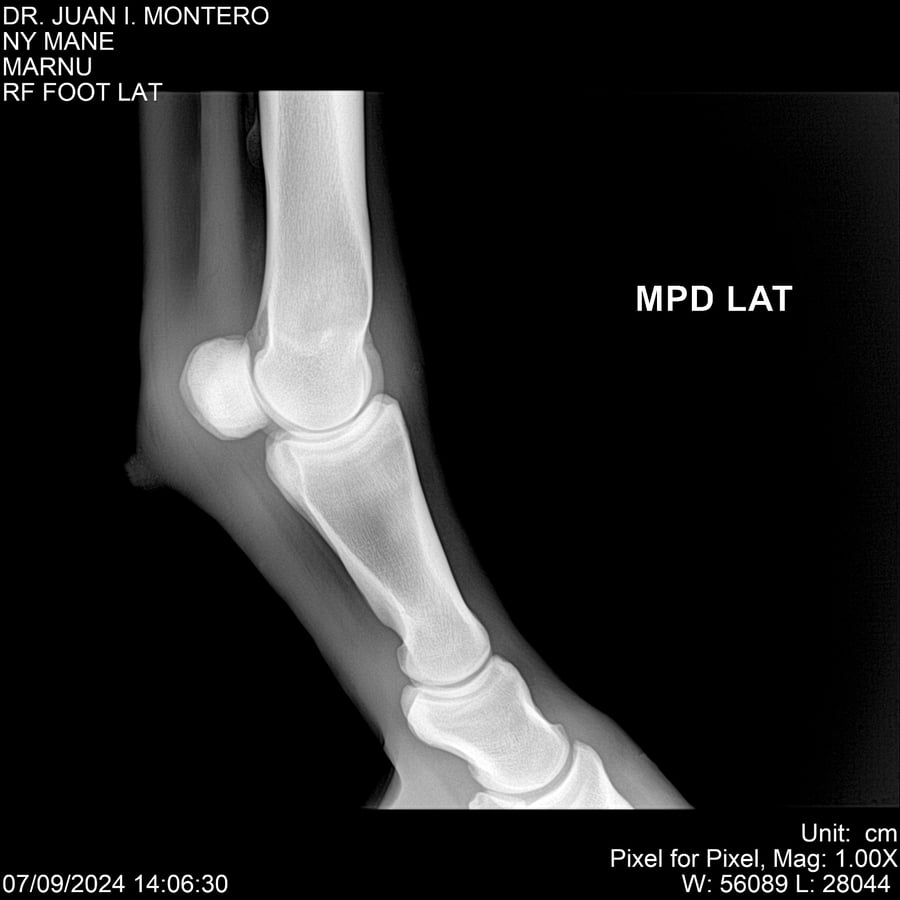

LOTE 20, NY MANE Lote Anterior Volver al remate Lote Siguiente Ficha Contacto Montevideo - Ficha del Lote Identificador: #282520 Categoría: Yeguarizos 76 Visualizaciones ClicData Contacto Empresa: Abelenda N. R., Walter Hugo Nombre*: Teléfono* : E-mail* : Mensaje Enviar Registrese gratis Este contenido Exclusivo está disponible sólo para usuarios registrados Ingresar